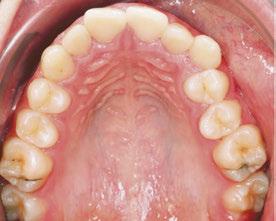

In my practice at Teeters Orthodontics in Peoria, Arizona, I have fully integrated Angel Aligner into my treatment protocols. One of the key innovations I utilize is the angelButton™, a unique feature designed to enhance sagittal bite correction and correct crossbites more efficiently and effectively. By incorporating these built-in buttons with elastics, I am able to achieve more predictable and efficient outcomes for my patients, improving their overall bite alignment with greater precision.